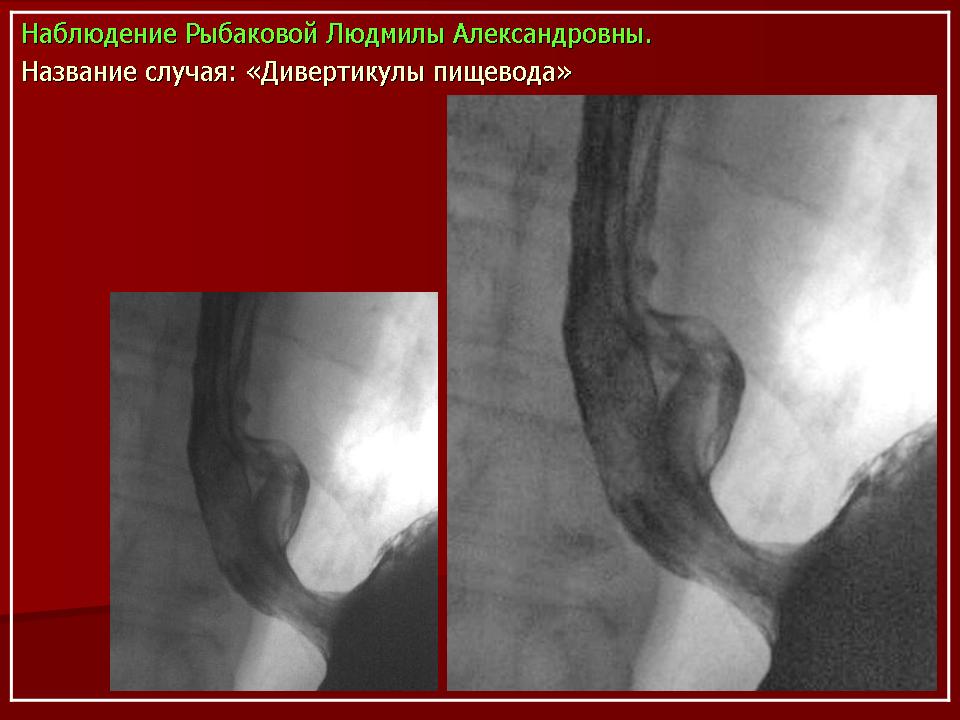

Клиническая картина, предварительный диагноз У большинства больных, особенно с небольшими дивертикулами, стойкие симптомы заболевания могут отсутствовать. Лишь эпизодически возникает дисфагия, чаще при поспешной еде, еде всухомятку. При дивертикулах больших размеров дисфагия возникает почти при каждом приеме пищи, в положении лежа может наблюдаться регургитация (обратное затекание) содержимого дивертикула в пищевод и глотку, срыгивание. Эти больные могут отмечать неприятный запах (вследствие разложения задержавшихся в пищеводе пищевых остатков). Основное значение для диагностики дивертикула имеет контрастное рентгенологическое исследование, при котором устанавливают дивертикул, определяют его размеры, форму, наличие или отсутствие в нем контрастной массы и пищевых остатков. Небольшие дивертикулы средней и нижней трети пищевода, в которых не задерживается контрастная масса, лучше выявляются при рентгенологическом исследовании пищевода в положении больного лежа. Небольшие бессимптомно протекающие дивертикулы часто являются случайной рентгенологической находкой при контрастном рентгенологическом исследовании, проводимом по другому поводу. Дивертикулы, соединяющиеся с пищеводом широким сообщением, выявляют при эзофагоскопии. Со временем дивертикулы нередко увеличиваются в размерах. При плохом опорожнении дивертикула (при мешкообразной форме, с дном, расположенным значительно ниже шейки дивертикула) в нем задерживается пища (особенно плохо разжеванные куски), которая может разлагаться; велика опасность возникновения дивертикулита, а затем - медиастинита. В дивертикулите могут задерживаться и проглоченные инородные тела (кусочки куриной или рыбьей кости и др.).

У большинства больных, особенно с небольшими дивертикулами, стойкие симптомы заболевания могут отсутствовать. Лишь эпизодически возникает дисфагия, чаще при поспешной еде, еде всухомятку. При дивертикулах больших размеров дисфагия возникает почти при каждом приеме пищи, в положении лежа может наблюдаться регургитация (обратное затекание) содержимого дивертикула в пищевод и глотку, срыгивание. Эти больные могут отмечать неприятный запах (вследствие разложения задержавшихся в пищеводе пищевых остатков). Основное значение для диагностики дивертикула имеет контрастное рентгенологическое исследование, при котором устанавливают дивертикул, определяют его размеры, форму, наличие или отсутствие в нем контрастной массы и пищевых остатков. Небольшие дивертикулы средней и нижней трети пищевода, в которых не задерживается контрастная масса, лучше выявляются при рентгенологическом исследовании пищевода в положении больного лежа. Небольшие бессимптомно протекающие дивертикулы часто являются случайной рентгенологической находкой при контрастном рентгенологическом исследовании, проводимом по другому поводу. Дивертикулы, соединяющиеся с пищеводом широким сообщением, выявляют при эзофагоскопии. Со временем дивертикулы нередко увеличиваются в размерах. При плохом опорожнении дивертикула (при мешкообразной форме, с дном, расположенным значительно ниже шейки дивертикула) в нем задерживается пища (особенно плохо разжеванные куски), которая может разлагаться; велика опасность возникновения дивертикулита, а затем - медиастинита. В дивертикулите могут задерживаться и проглоченные инородные тела (кусочки куриной или рыбьей кости и др.).

Наддиафрагмальный дивертикул